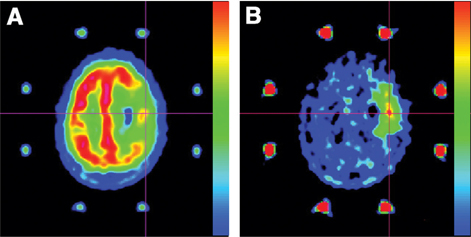

18F-FDG is useful for differentiating high-grade gliomas from other types of brain tumors (18). In the specific setting of glioblastomas, 18F-FDG is particularly sensitive at the initial stage of the diagnosis (19, 20), an example of which is given in Figure 1. In a study involving 31 newly diagnosed glioblastomas, Colavolpe et al. found an uptake of 18F-FDG in these tumors with a tumor-to-background ratio max (TBRmax) of 1.4±0.8 (12). However, differential diagnosis at the initial stage with 18F-FDG may be difficult to achieve due to the low specificity of this radiotracer. Indeed, brain lymphomas can display a higher glucose metabolism uptake than high-grade gliomas (21). Moreover, nonneoplastic neurological diseases can mimic brain neoplasms on 18F-FDG, including pyogenic abscesses, tuberculosis, fungal infections, or sarcoidosis (22). Studies comparing the 18F-FDG and amino acid tracer uptake in the assessment of brain tumors demonstrated significantly higher tumor to brain contrast with amino acid PET than with 18F-FDG (2325), demonstrating a higher sensitivity of amino acid tracers for glioblastoma detection.

Fig 1

Figure 1 Primary diagnosis of a right frontal glioblastoma in a 79-year-old man following acquisition of axial slices of T1-weighted gadolinium-enhanced MRI (left side) and 18F-FDG PET (right side). The right frontal glioblastoma is contrast-enhanced on MRI (white arrow) and shows an extensive uptake of 18F-FDG PET (white arrow), despite the high uptake in surrounding normal brain tissue.